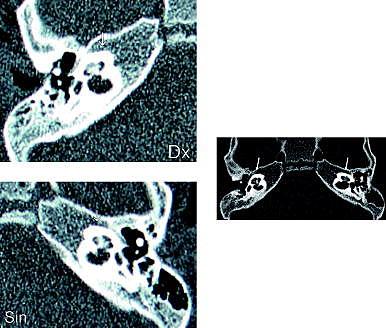

En computertomografi viste bilateralt udtalt sklerosering omkring cochlea, buegange og pori (angivet med pile). Patienten blev indstillet til bilateral implantation af elektroder i cochlea (Cochlear Implant (CI)) mhp. elektronisk stimulation af nervus cochlearis for at opnå hørelse. Hun blev opereret tre måneder efter sygdomsdebut, hvor det pga. den udtalte sklerosering kun var muligt at introducere seks ud af 22 mulige elektroder på højre side og ingen elektroder på venstre.